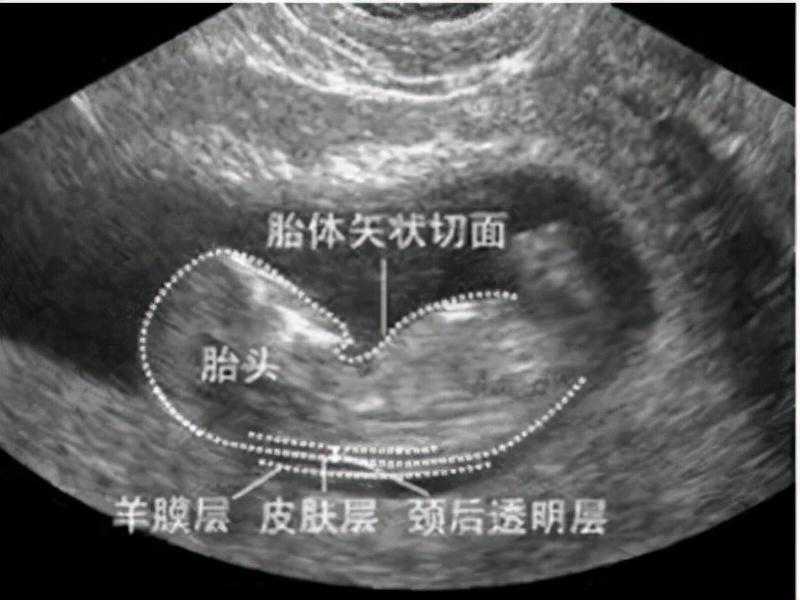

NT是通过b超的形式去检查胎儿颈后透明带层的厚度,通过这个厚度去筛查胎儿染色体异常的风险。正常的话,胎儿颈后透明带层的厚度小于3mm,颈后透明带层越厚代表胎儿染色体异常的风险越高,这个检查需要在11~13+6周进行。